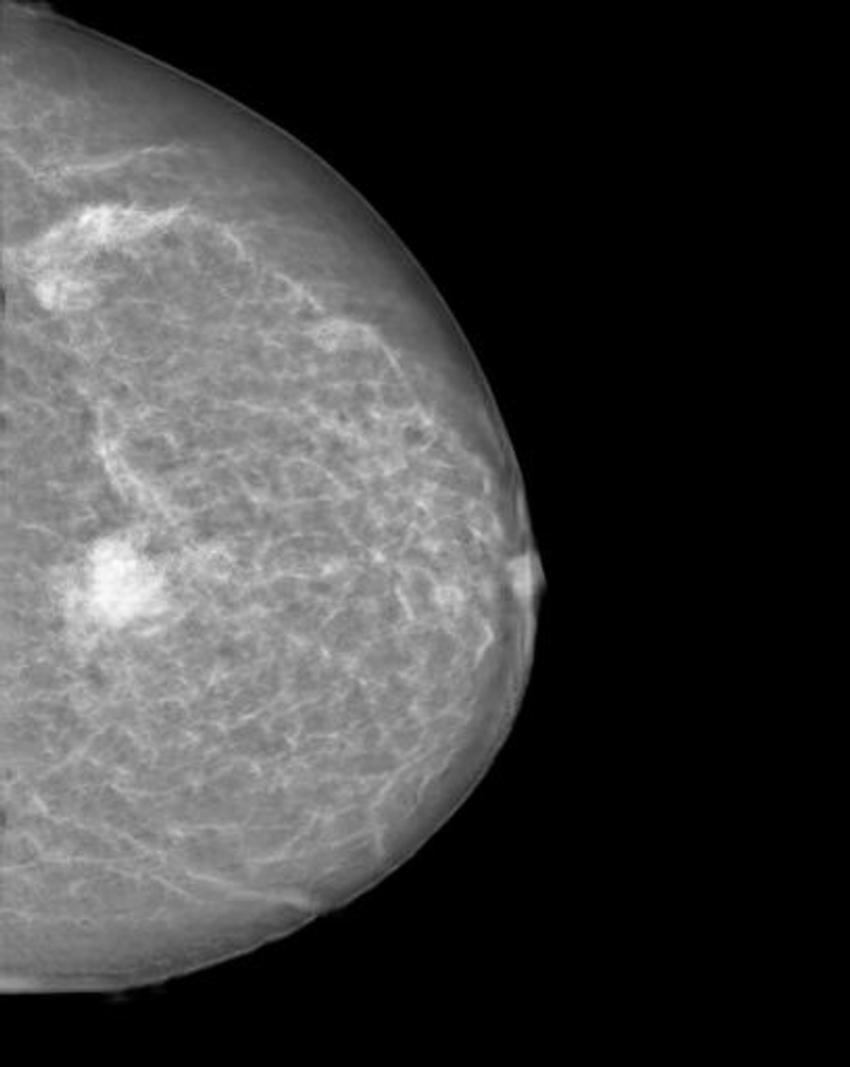

Figure 1. Mammogram of a healthy breast.

High-res (TIF) version

Figure 2. Manipulated mammogram of breast in Figure 1 with a neural-network-generated mass.

The researchers trained a cycle-consistent generative adversarial network (CycleGAN), a type of artificial intelligence application, on 680 mammographic images from 334 patients, to convert images showing cancer to healthy ones and to do the same, in reverse, for the normal control images. They wanted to determine if a CycleGAN could insert or remove cancer-specific features into mammograms in a realistic fashion.

The images were presented to three radiologists, who reviewed the images and indicated whether they thought the images were genuine or modified. None of the radiologists could reliably distinguish between the two.

"Neural networks, such as CycleGAN, are not only able to learn what breast cancer looks like," Dr. Becker said, "we have now shown that they can insert these learned characteristics into mammograms of healthy patients or remove cancerous lesions from the image and replace them with normal looking tissue."